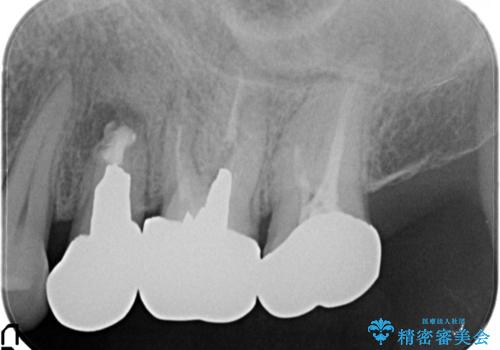

[20代男性] インプラント 失った歯の治療